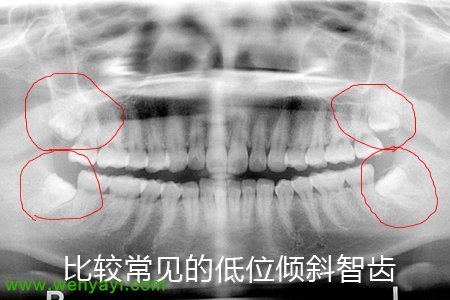

科普-智齿横着长七八年了也不疼要不要拔掉,不拔会有什么危害吗?